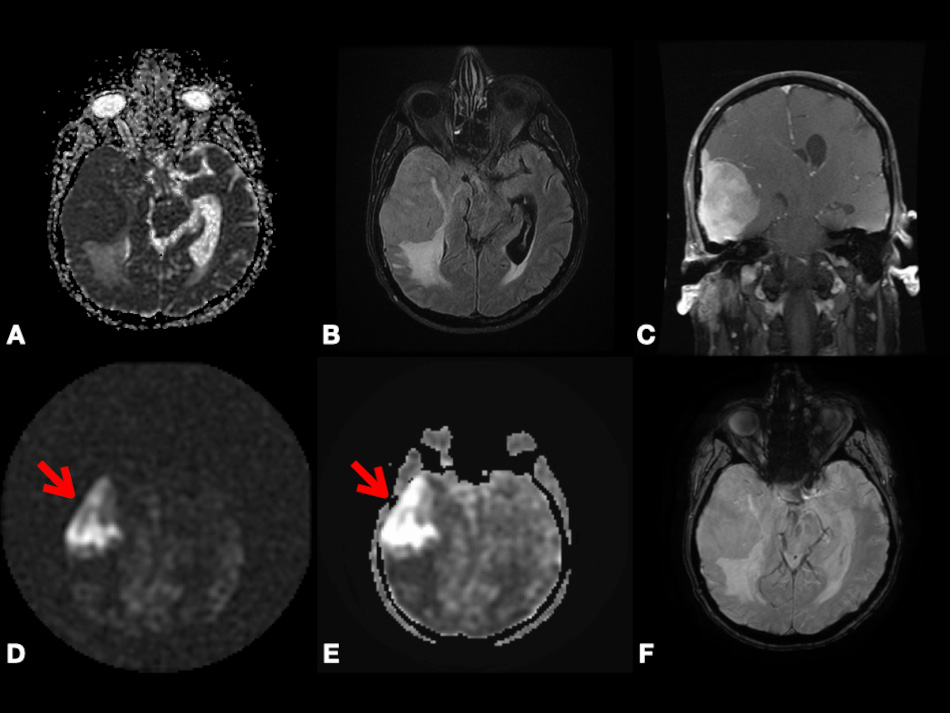

In contrast to conventional MRI, which delineates the anatomical structures and shows gross changes in the structure of the tumor, advanced MRI techniques represent dynamic physiological properties of tissue, which may be helpful in differentiating undiagnosed lesions based on properties including vascularity, cellularity, and metabolism [7, 8, 9]. The term advanced MRI techniques is used throughout this article to refer to dynamic contrast-enhanced (DCE) MRI, dynamic susceptibility contrast (DSC) MRI, diffusion-weighted imaging (DWI), arterial spin labeling (ASL) MRI, and blood oxygen level-dependent functional MRI (BOLD fMRI). In Figs. 1,2, we present different MRI images of two cases with different brain lesions including right frontal lobe oligodendroglioma (WHO grade II) and left lateral ventricle cavernous malformation. These two figures demonstrate the main differences between conventional MRI which delineates the anatomical borders of the brain lesions and advanced MRI techniques which demonstrate the internal physiologic features of different tumors, such as their vascularity, cellularity, perfusion, oxygenation, and microstructure.

Fig. 1.Right frontal lobe oligodendroglioma (WHO Grade 2). Axial ADC map (A), FLAIR (B), and post-contrast T1-weighted (C) images depicting non-enhancing tumor with T2 prolongation in gray and white matter and increased diffusivity (i.e., shine-through artifact). Axial pcASL source data (D), color-coded CBF map (E) from pcASL data, and color-coded rCBV map (F) from DSC data depicting no hyperperfusion. Abbreviation: ADC, Apparent diffusion coefficient; FLAIR, Fluid attenuated inversion recovery; pcASL, Pseudo-Continuous Arterial Spin Labeling; CBF, cerebral blood flow; rCBV, relative cerebral blood volume; DSC, Dynamic susceptibility contrast MR imaging.

Fig. 2.Left lateral ventricle cavernous malformation. Axial T2-weighted (A), pre- and post-contrast T1-weighted (B,C), and SWI (F) images depicting lesion with heterogenous enhancement, heterogenous predominantly hyperintense signal, peripheral hemosiderin rim, and extensive blooming. Axial pcASL source data (D) and color-coded CBF map (E) depicting no hyperperfusion. Abbreviations: SWI, Susceptibility weighted imaging; pcASL, Pseudo-Continuous Arterial Spin Labeling; CBF, cerebral blood flow.